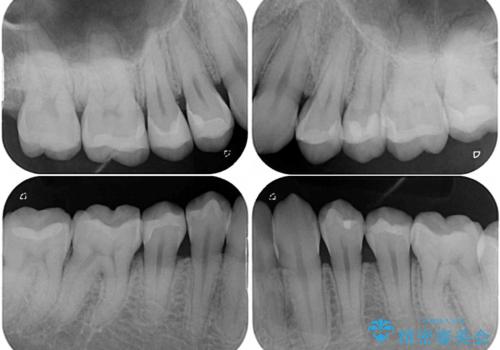

- 奥歯の目立つ銀歯と上下前歯の叢生と隙間を気にして来院された患者様です。

開咬の治療は、前歯を閉じるように動かすとともに、上下臼歯を圧下(骨内にめり込ませる)させることで進めて行きます。

インビザラインは臼歯の圧下を効果的に行えるため、インビザラインを用いて矯正治療を行うこととしました。

銀歯については、矯正治療により咬合関係を改善し、矯正治療後半に修復治療を行うこととしました。

修復治療後に細かい部分をインビザラインで再度仕上げるプランとしました。